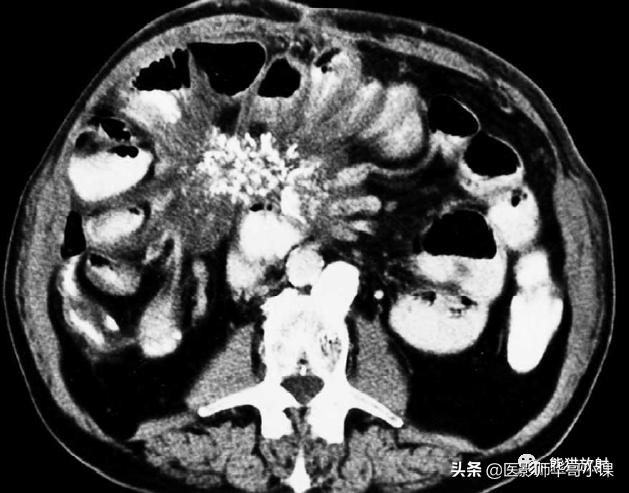

肠系膜脂膜炎的特征性CT表现 为肠系膜根部边界清晰、密度不均的脂肪肿块,包绕肠系膜血管,可推移或不推移邻近肠襻,但不侵犯邻近肠襻,血管周围可见低密度环(图)。T2WI上呈低信号包膜,静脉注射对比剂后可见强化。

肠系膜脂膜炎。患者腹痛,增强CT(A)和真实稳态进动快速成像(true-FISP) MRI(B) 显示一个边界清晰的脂质肿块(大箭),从小肠系膜根部向左侧腹部延伸,包绕肠系膜血管,无扭转。注意血管周围的晕环(小箭)